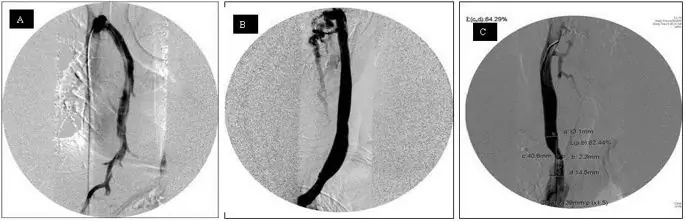

figure8

Катетерная венография азигоз и внутренних яремных вен. Пример нормального открытого просвета азигозной вены (A) и левой внутренней яремной вены (IJV) (B). Значительный стеноз проксимального отдела правого IJV (C).